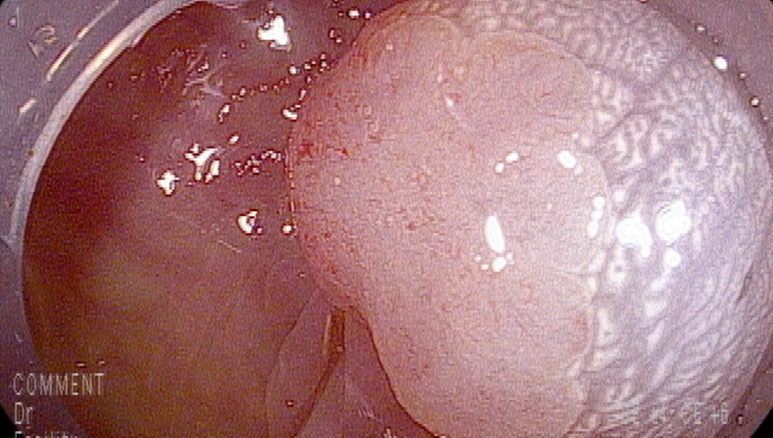

마지막 유경성 거대 용종을 제외하고 점막 소구 패턴(pit pattern)이 불규칙하게 관찰되어(Vi) 고등급의 선종 혹은 점막암을 의심하여 충분히 융기시켜 경계가 확실히 포함되고 한조각으로 완전 절제하기 위해 넓게 절제함

9 mm 크기

19-20 mm 크기의 유경성(목이있는) 용종은 클립을 적절히 사용하여 출혈예방함